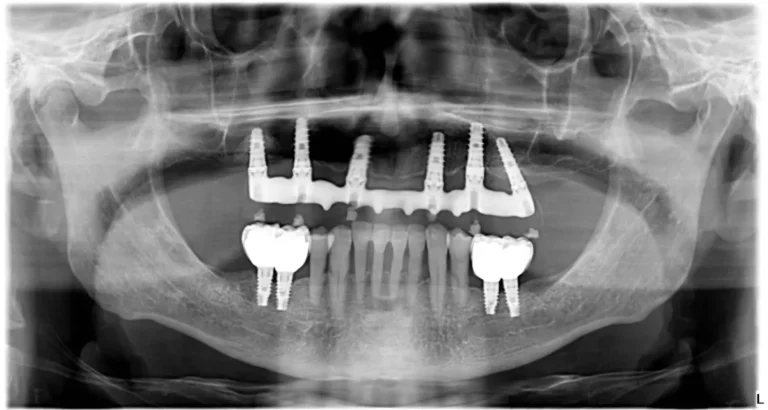

L’implantologia All-On-4 e quella All-On-6 sono tecniche innovative utilizzate per riabilitare completamente l’arcata dentale in pazienti edentuli (senza denti) o con denti gravemente compromessi, consentendo di ottenere un nuovo sorriso in tempi relativamente brevi.

La tecnica All-On-4 prevede l’inserimento di quattro impianti dentali strategicamente posizionati nell’osso mascellare o mandibolare. Ecco le caratteristiche principali:

- Posizionamento degli impianti: due impianti vengono inseriti verticalmente nella parte anteriore della mascella o della mandibola, mentre i due impianti posteriori vengono inclinati (di solito a 30-45 gradi) per massimizzare la stabilità e l’ancoraggio. Questo consente di sfruttare le aree ossee più dense.

La tecnica All-On-6 utilizza sei impianti dentali per supportare una protesi fissa. Le caratteristiche principali sono:

- Posizionamento degli impianti: come per l’All-On-4, gli impianti vengono posizionati in modo strategico per ottimizzare la stabilità, ma con due impianti aggiuntivi per una maggiore distribuzione delle forze masticatorie.